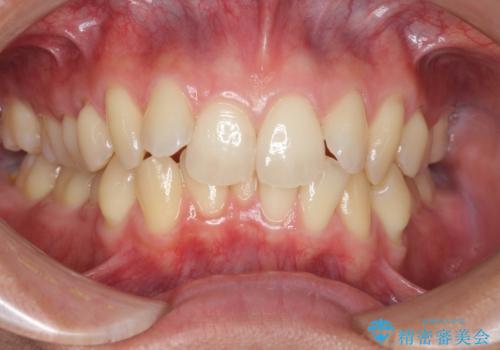

過蓋咬合・上顎前突・叢生を改善するマウスピース矯正

- 前歯のがたつき、不揃いさの改善を求めて来院されました。

・前歯の深い噛み合わせ (過蓋咬合)

・上顎前突(Angle Class2)

・叢生(がたつき)